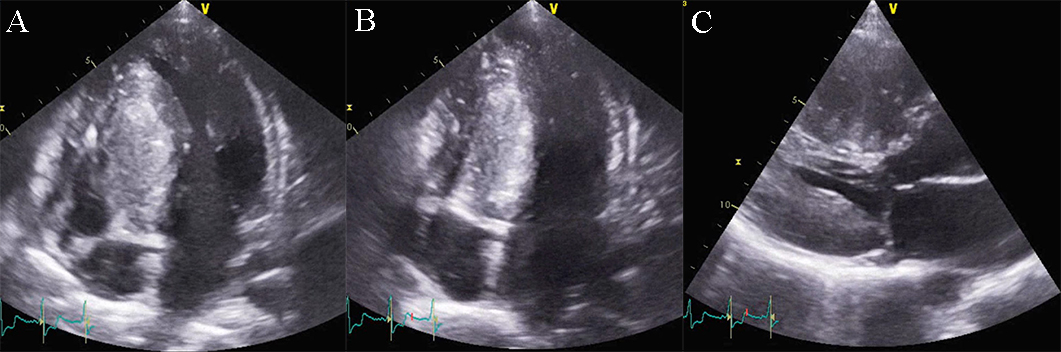

Left ventricular non-compaction cardiomyopathy (LVNC) is characterized by an LV

wall with prominent trabeculae and deep intertrabecular recesses filled with

blood resulting in two layers of myocardium: a thickened noncompacted endocardial

layer and an external, subepicardial thin compacted layer. The diagnosis of LVNC

is obtained through morphologic criteria on transthoracic echocardiography (Fig. 12 and Appendix Video 7). The echocardiographic appearance of isolated LVNC is very

heterogeneous and it can include dilated, hypertrophic or restrictive types. The

Jenni criteria for echocardiographic diagnosis of LVNC are the validated imaging

benchmark [67]. The necessary parameters are assessed using the parasternal

short-axis view at the base, midventricular, and apical levels, and for a

positive diagnosis all four of the following criteria must be met: (1) two

myocardial layers: a thin compacted exterior (epicardial) and a markedly

thickened endocardial layer with several prominent trabeculations and deep

recesses with a maximum ratio of noncompacted to compacted myocardium greater

than 2:1 at end-systole in the parasternal short-axis view; (2) evidence of flow

within the deep intertrabecular recesses through color Doppler; (3) presence of

prominent trabecular meshwork in the LV apex or midventricular segments of the

inferior and lateral wall; (4) maximal systolic compact thickness of

Fig. 12.Echocardiographic non-compaction cardiomyopathy. (A) 2D short axis view, at the level of the apex, showing a meshwork of trabeculae. (B) 2D Apical 4 chamber view showing dilation of the left ventricle, and apical trabeculation. A video of the apical 4 chamber view is available online (Appendix Video 7).